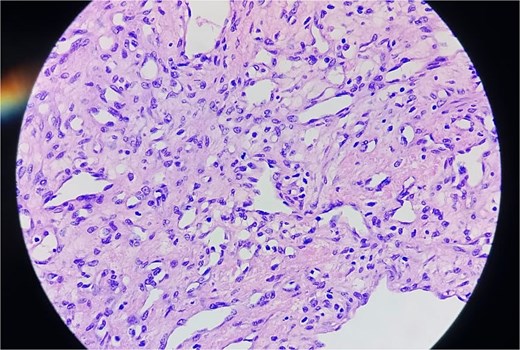

A 2-month-old female infant was admitted with respiratory distress characterized by tachypnea, and cough, along with poor feeding and systemic symptoms such as fever and episodic diaphoresis. At 25 days of age, she had previously been hospitalized for similar symptoms, during which a massive pericardial effusion was identified. Initially, an extracardiac mass was suspected. Despite undergoing two pericardiocenteses and resuscitation after two post-cardiac arrest events, her clinical status continued to deteriorate, and she was referred for urgent surgical intervention due to cardiogenic shock from pericardial tamponade. On examination, she appeared pale with respiratory distress, intercostal retractions, pulsatile hepatomegaly (2 cm), splenomegaly (1 cm), and tachycardia (160 bpm). Laboratory findings showed hyponatremia (125 mmol/L). TTE demonstrated cardiomegaly, bilateral pleural effusion, and a massive pericardial effusion measuring 24–28 mm circumferentially. A 2.7 cm mass adjacent to the anterior RA wall and atrioventricular (AV) groove was identified (Fig. 1). Due to her unstable condition, CT imaging was deferred. An emergent median sternotomy revealed a severely distended pericardium containing copious effusion (Fig. 2). Upon opening the pericardium, immediate hemodynamic improvement was observed. The mass was visualized infiltrating the RA anterior wall and AV groove (Fig. 3). Total cardiopulmonary bypass (CPB) was initiated using aortic and bicaval cannulation. Following cardiac arrest with antegrade cold blood cardioplegia, the RA was incised posterior to the tumour. The lesion extended beyond the AV groove, precluding complete excision due to anatomical constraints (Fig. 4). Subtotal (debulking) resection was performed (Figs 4 and 5), and the RA anterior wall was reconstructed with a bovine pericardial patch (Fig. 6). The patient was successfully weaned from CPB, and the remainder of the surgery was uneventful. The infant was extubated within 48 hours and discharged after a 14-day hospital stay, with subsequent TTE showing satisfactory cardiac function. Histopathological evaluation confirmed a benign capillary hemangioma characterized by lobulated reddish tissue with compact capillary proliferation, fibrous septae, and stromal hyalinization. Immunohistochemical staining was positive for CD31 and CD34, confirming endothelial origin and ruling out malignancy (Fig. 7). At one-year follow-up, the patient remained in excellent general health with no signs of recurrence.

Complete resection of CHs is often unachievable due to anatomical constraints. In our patient, tumour extension into the AV groove made complete removal impossible. Partial (debulking) resection was performed to restore hemodynamic stability, a valid approach supported in cases where tumour location precludes radical excision [12]. Histopathology confirmed a capillary hemangioma with immunohistochemical positivity for CD31 and CD34, confirming its vascular origin [13, 14].